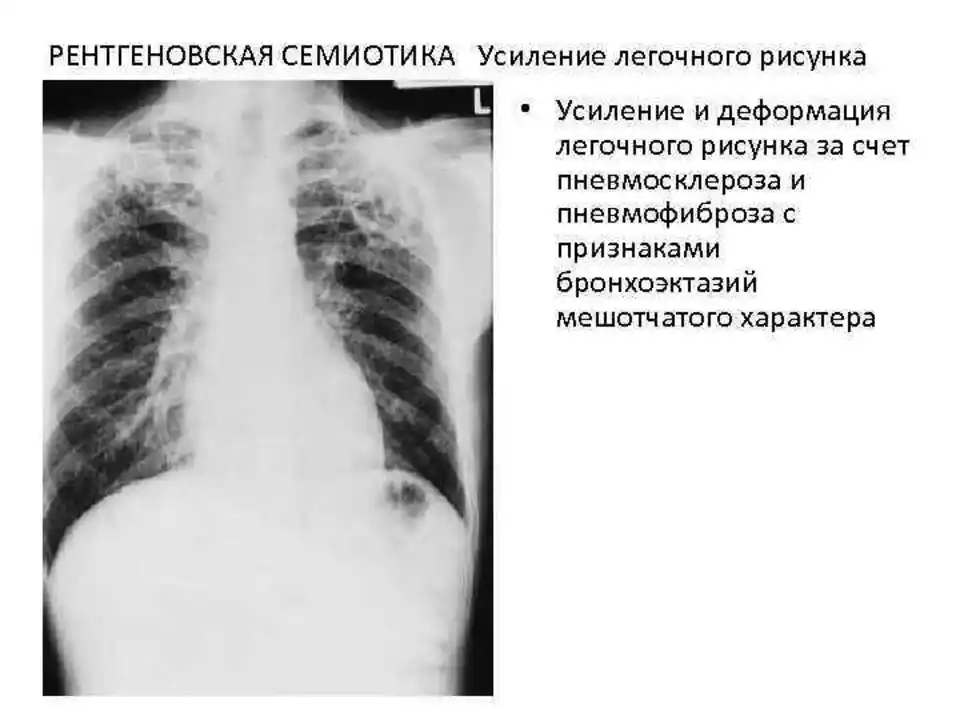

Ячеистая деформация легочного рисунка: медицинская визуализация